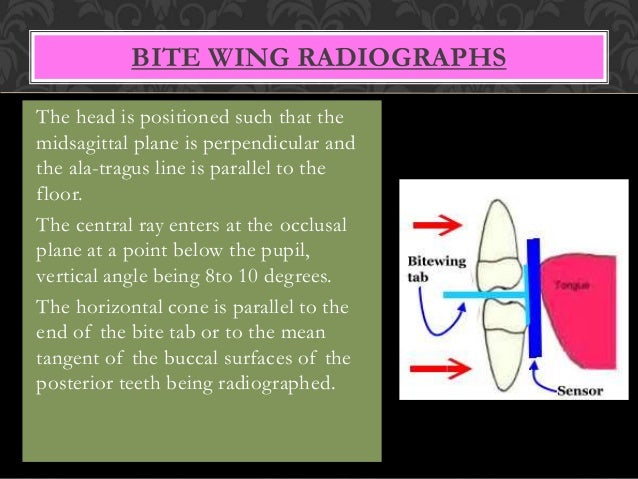

Tragus of the ear must be aligned with the plastic guides ala tragus line should be 50 from level positioning the patient position the patient panoramic lead apron must be used position apron high in front to protect the thyroid apron should be lower in back to expose the neck. Discussion most panoramic x ray machines use the ala tragus line for patient positioning whereas a few use the orbito meatal line. Ala tragus line is one of the common extra oral soft tissue land mark utilized in dental clinics for occlusal plane orientation. Here the occlusal plane should be mildly curved upward to make a smile like line.

The angle between this line and the horizontal plane is 3on the panorex and 4on the. Focal trough layer that area between the x ray source and the image receptor that will be imaged distinctly on the panoramic. In other words the ala of the nose should be slightly inferior to the height of the tragus. These zones are as follows.

Important in determining the correct position of the patient s head. Exposure was 80 to 90 kv at 10 ma for 1 5 to 2 seconds in accordance with the subject s physical. The panorex i s. To achieve the correct vertical angulation the head must be positioned upright and symmetrical with the ala of the nose just inferior to the height of the tragus.